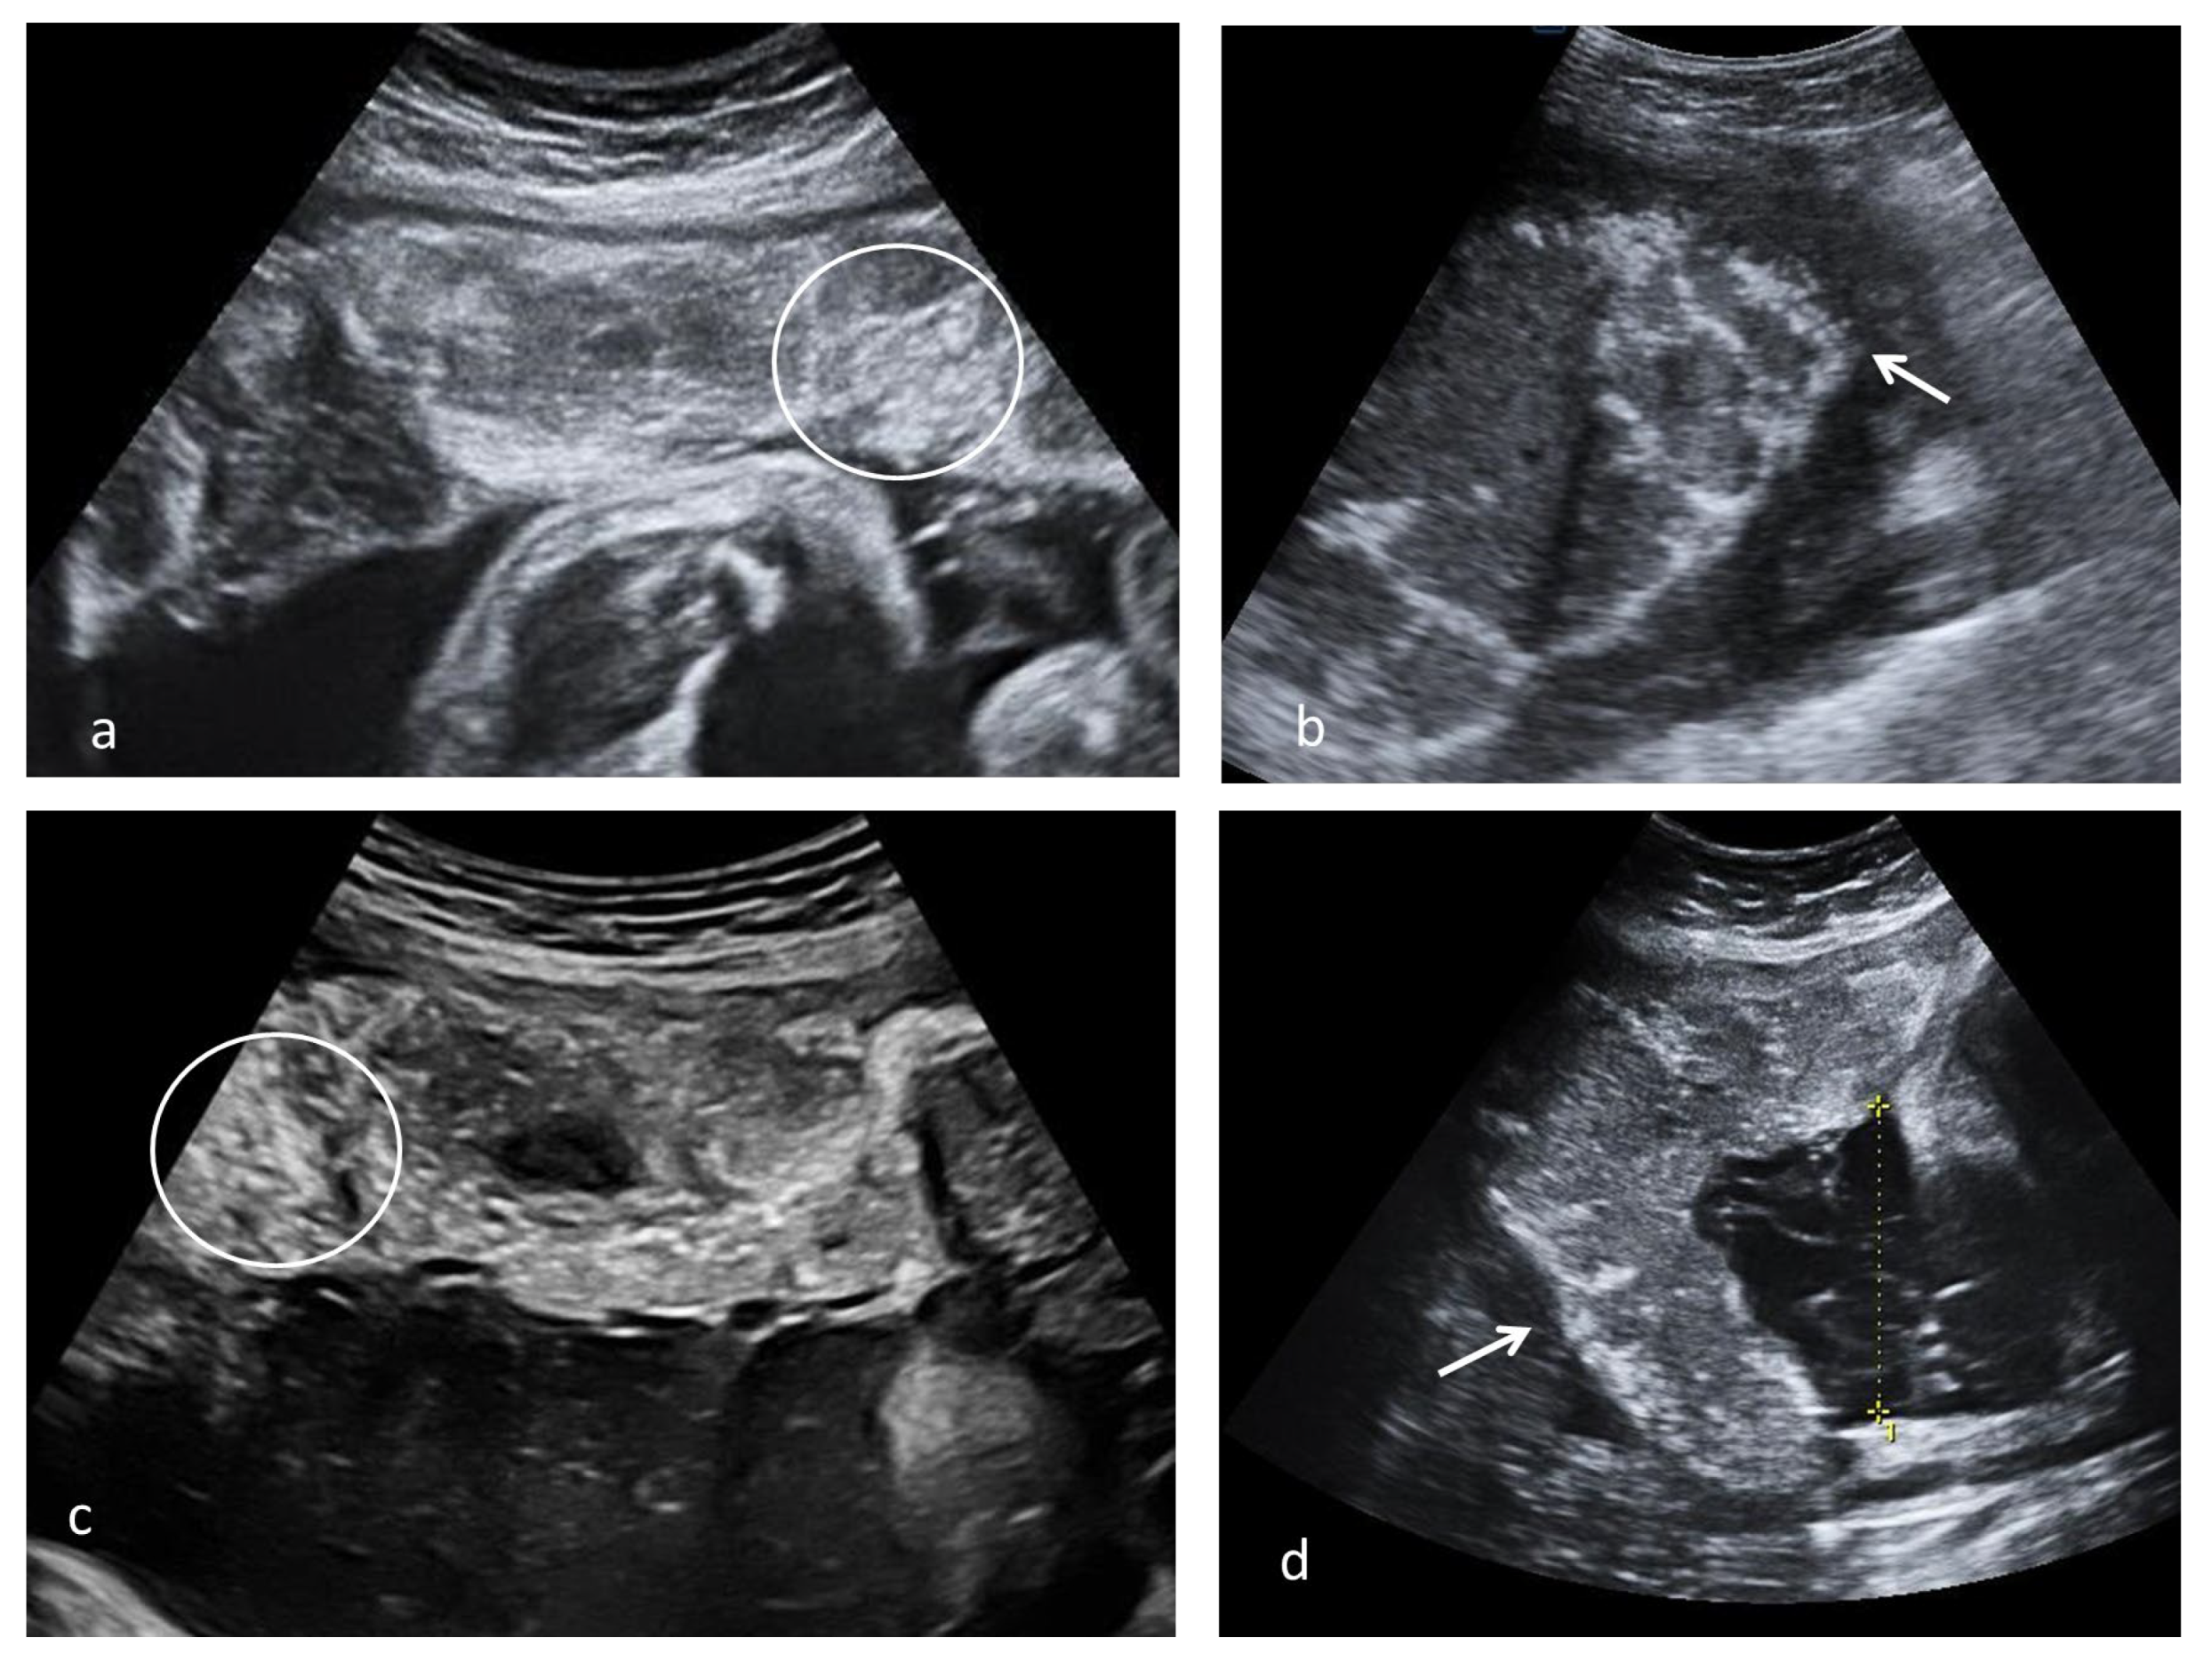

Various aspects of placental remodeling is rendered in Figure 3.

Placental ultrasound placental aspect observed after SARS-CoV-2 infection; (a) multiple echogenic foci occupying the entire placental volume and the matte glass appearance in 37 weeks of gestation (WG) second para with SARS-CoV-2 infection at 13 WG, natural birth (circle); (b) diffused echogenic foci and continuous white basal line (arrow) in a 39 WG primigravida with SARS-CoV-2 infection at 20 WG, natural birth; (c,d) multiple echogenic foci occupying the entire placental volume (circle), hypoechoic lacunae and white line (arrow) in a 38 WG primigravida with SARS-CoV-2 infection at 26 WG, caesarian section due to intrapartum fetal distress.